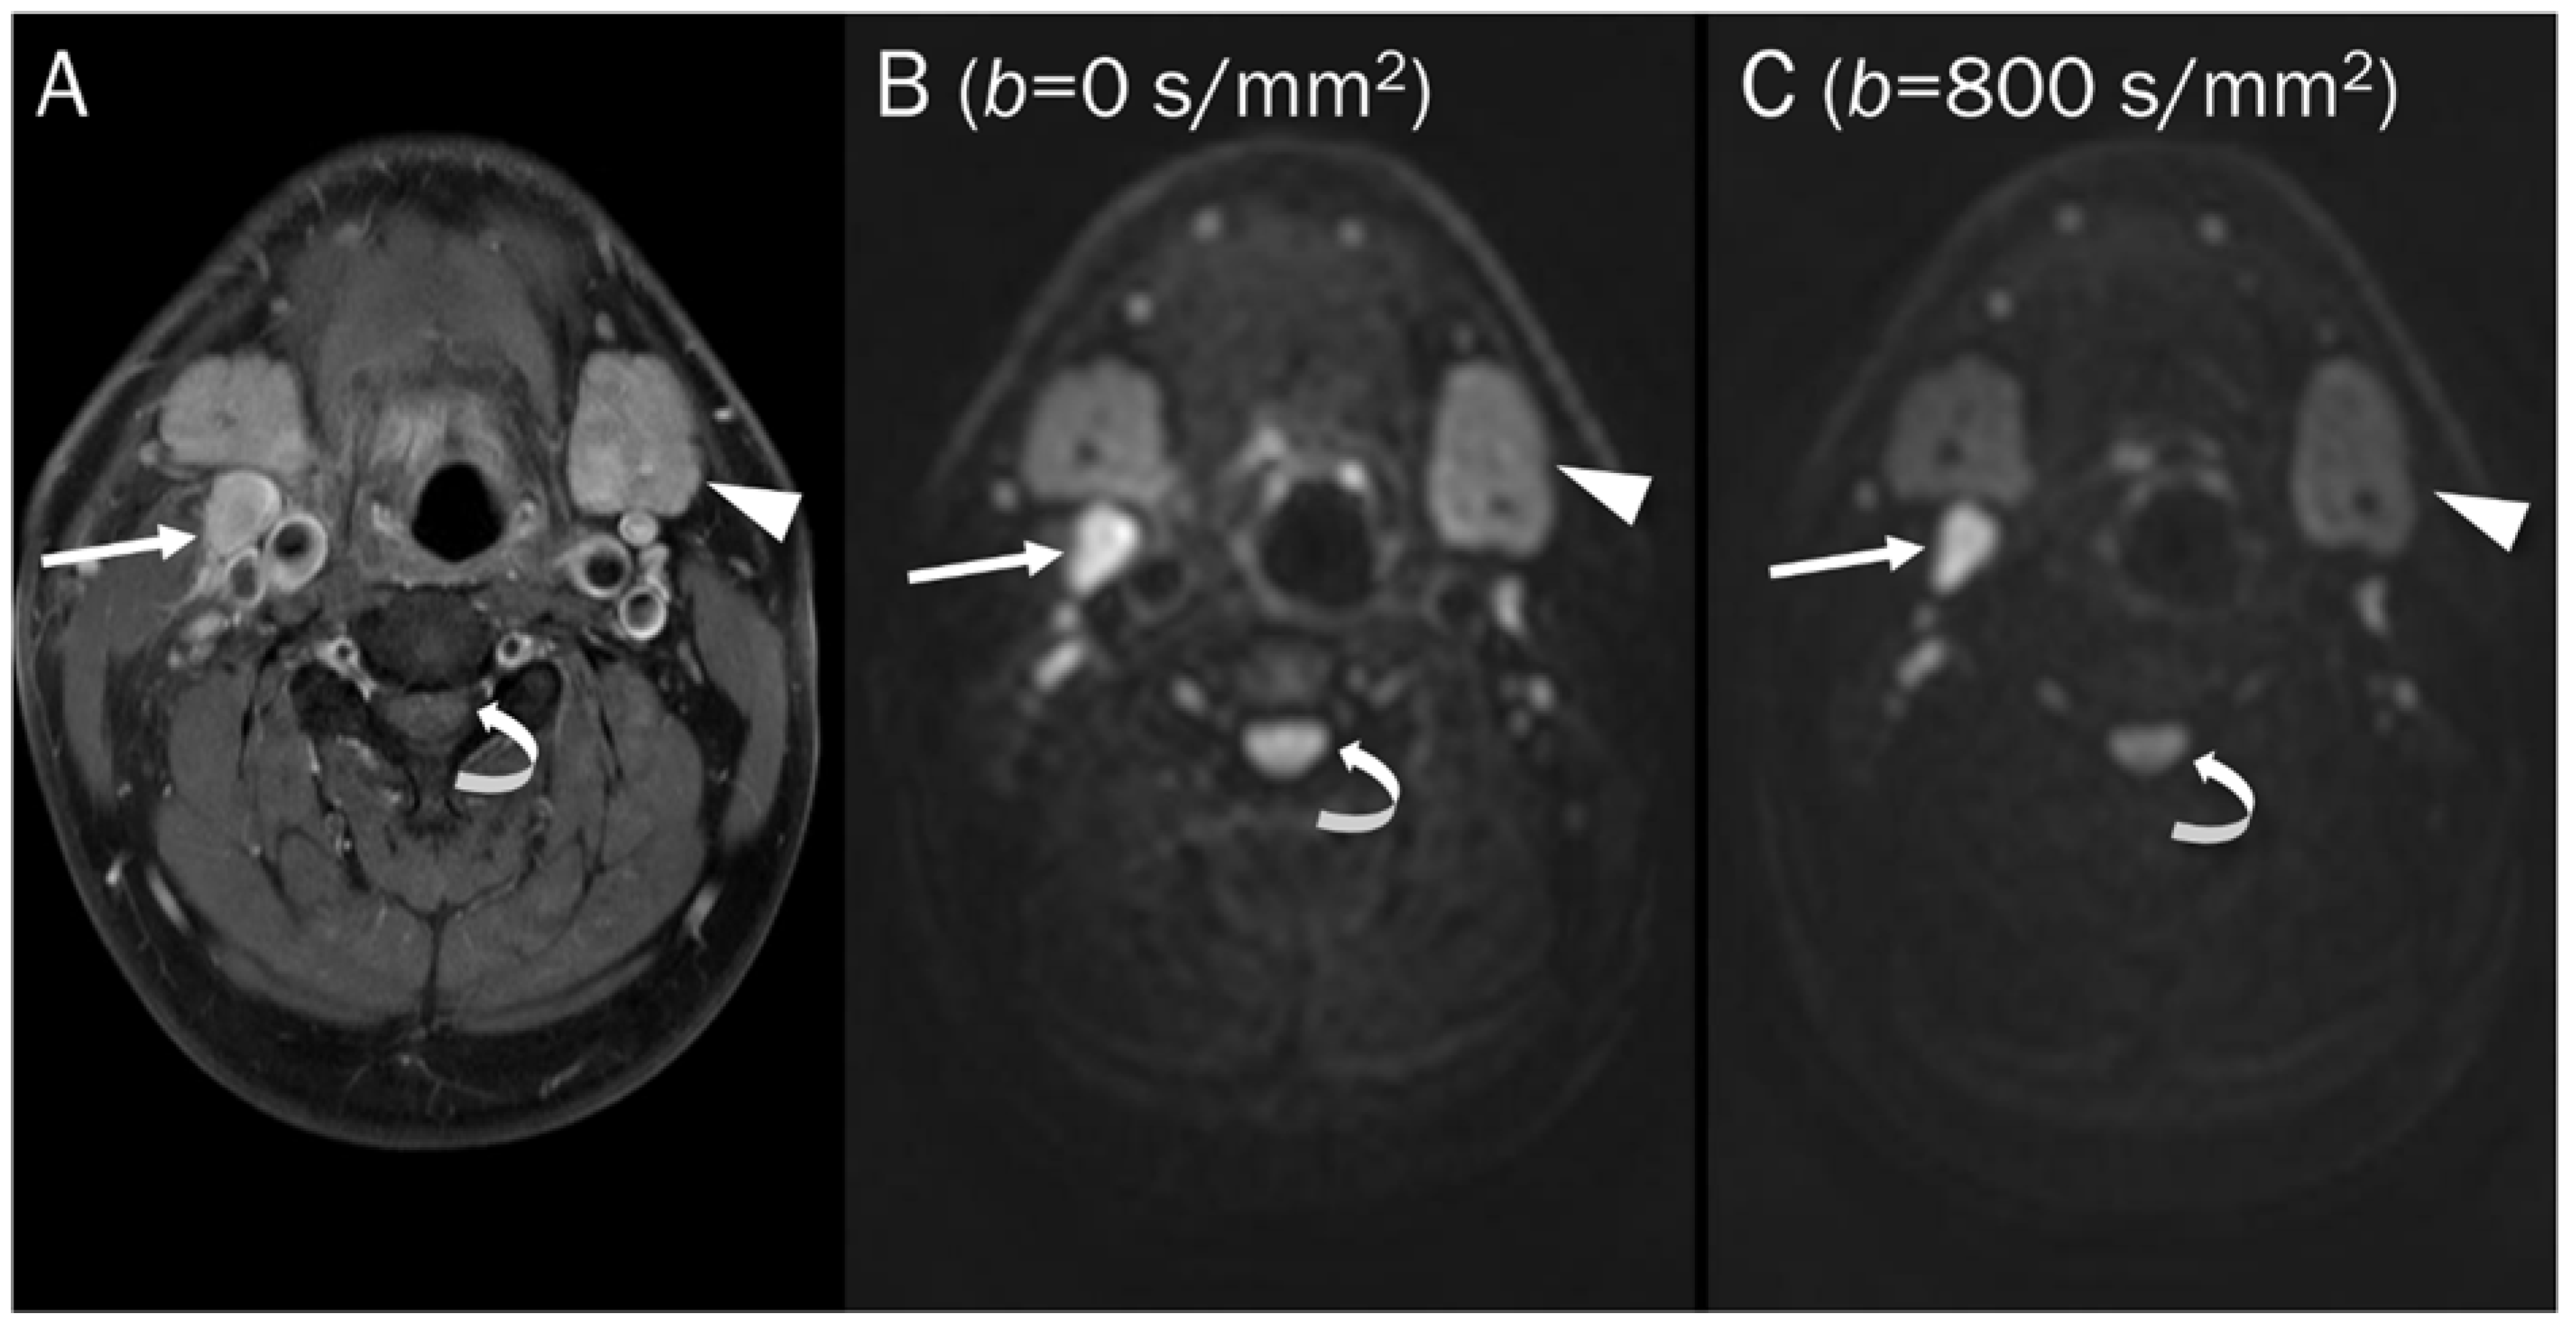

7.3. Benign Bone and Soft Tissue Tumors